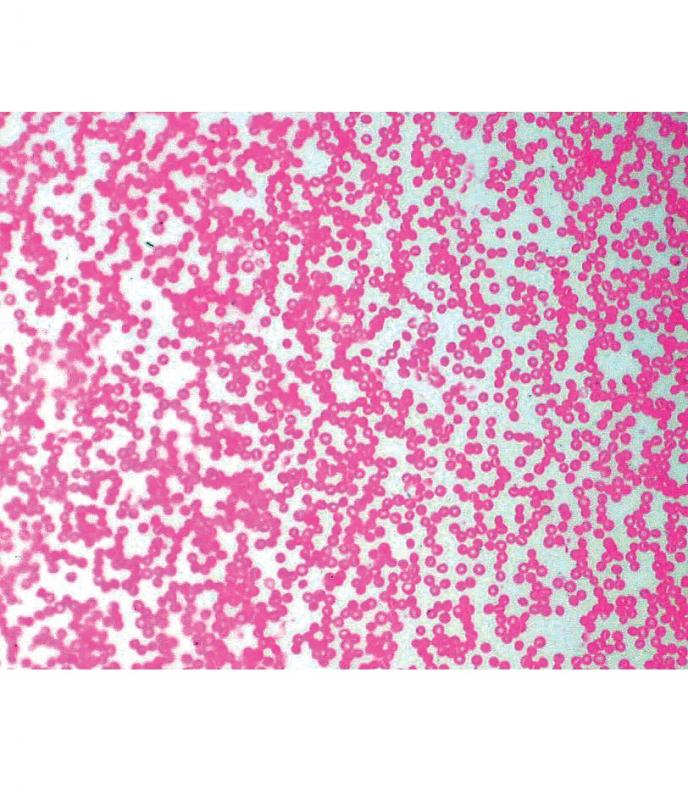

Préparation microscopique: Sang humain (giemsa)